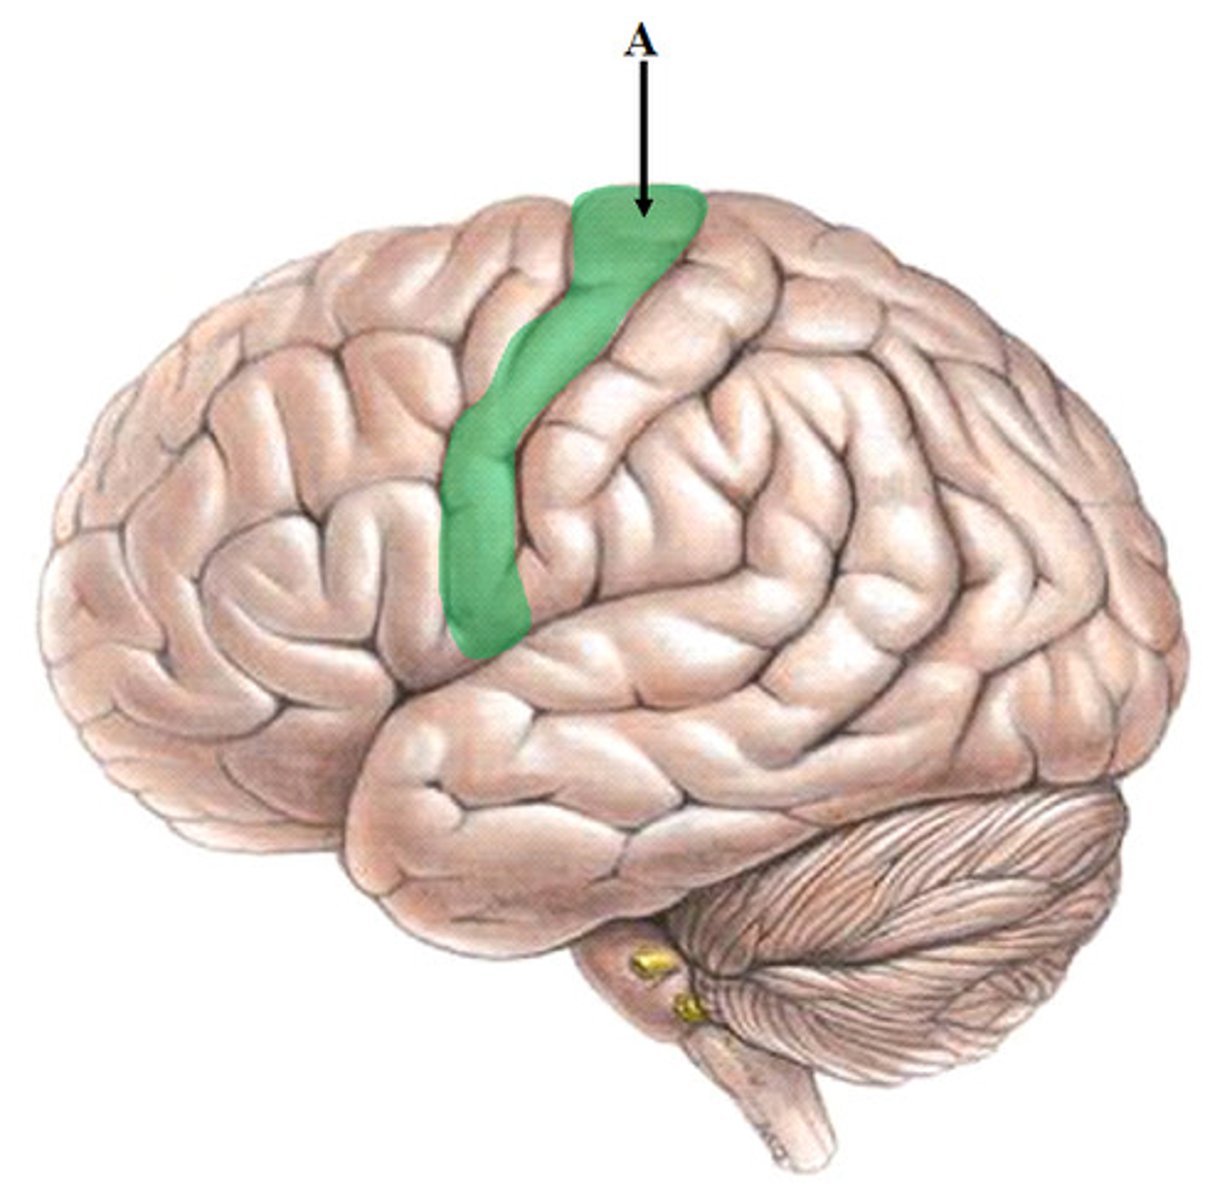

Somatomotor Area

Somatosensory Area

Central Sulcus